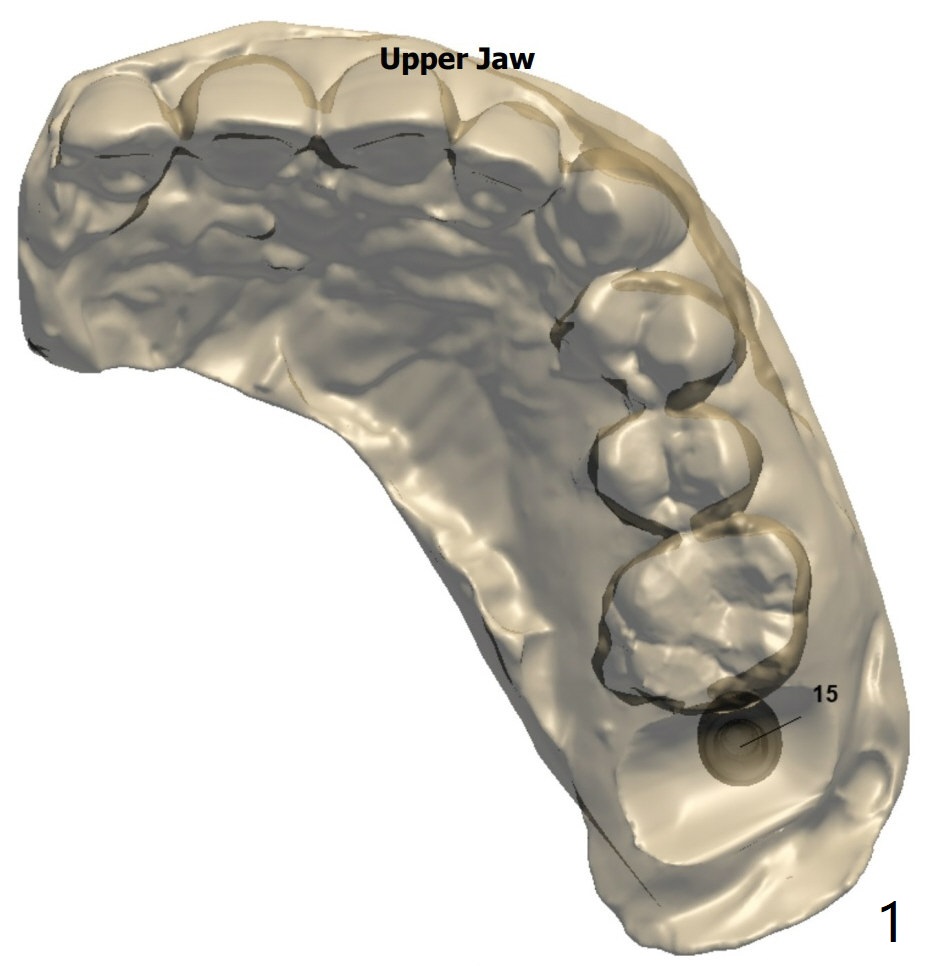

Return to Protect Graft Oral Scanner